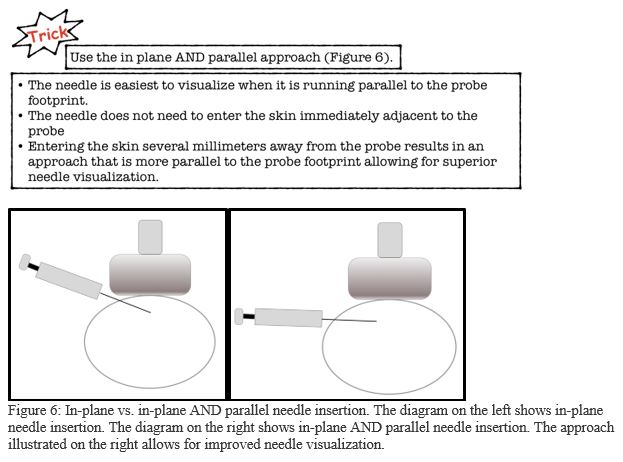

6. Inject the anesthetic (Figure 7)